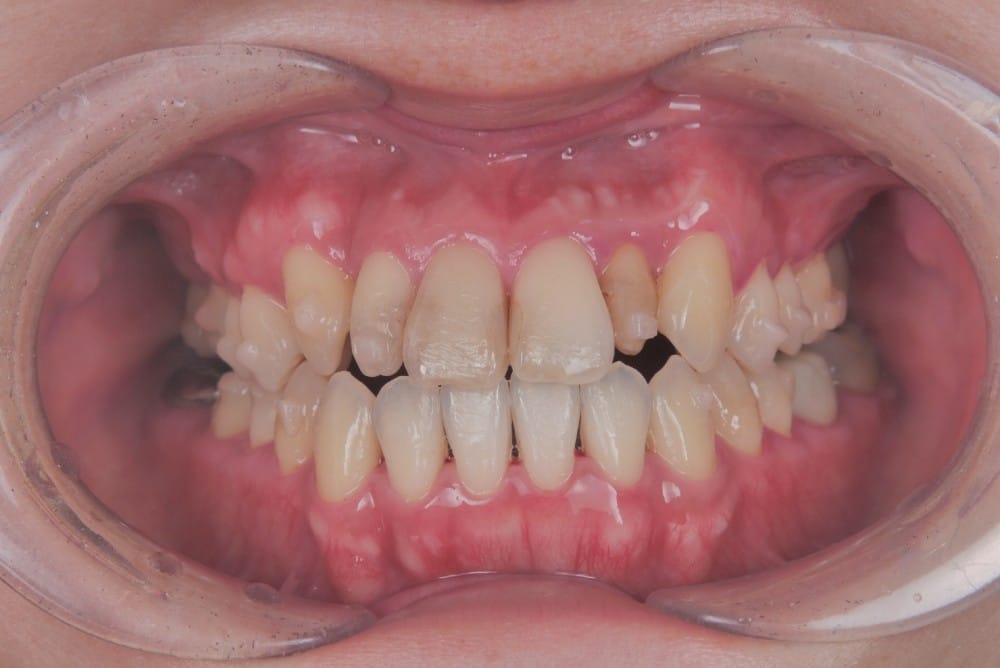

最後の画像のように奥歯のズレが1本以上あるケースでは、歯列矯正のみでの受け口の改善は困難と判断することが多いです。

この子は、中学生の女の子で、受け口、横顔が気になるとのことでご来院されました。

治療前の様子

分析をしますと

- 骨格的な上下あごの前後差は中等度

- 噛み合わせの位置も下あごの奥歯が半分くらい前にズレていた

- 上の前歯が前に傾斜、下の前歯が内側に傾斜しているにもかかわらず、受け口

というケースで、外科的な処置も検討するようなケースでした。

患者さまに外科的な手術の選択肢も提示しましたが、希望されず、横顔の変化はおそらく起こらないことを納得の上、治療をスタートいたしました。

このような奥歯の移動量が大きい症例では、マウスピースだけでは難しいことがあり、カリエールとよばれる装置を補助的に使用し、上下の噛み合わせの前後関係を整えることで、手術を行わずに機能面と見た目の両方が改善することがあります。

一時的に前歯は噛み合わせが開いていますが、受け口の矯正では、最終段階で前歯ばっかりあたって奥歯がしっかり噛まないということも起こりやすいので、あえて狙って動かしています。

ここから上下透明なマウスピースに変え、仕上げていきました。

治療後の写真

矯正治療によって前歯の被さりを改善することで、口元の突出感が減り、横顔がやわらかい印象に変化しました。